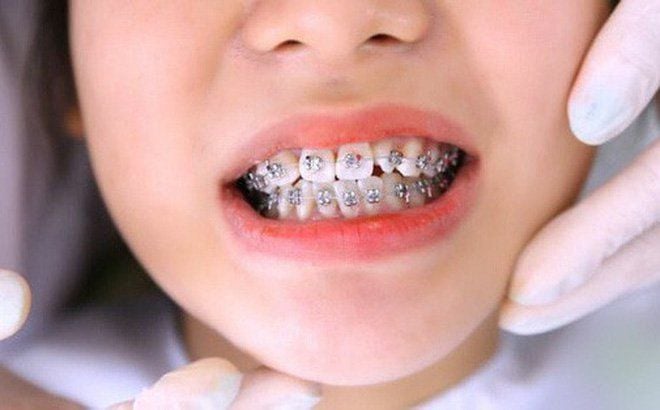

Niềng răng đóng khoảng:

- Trong trường hợp thiếu mầm răng bẩm sinh, niềng răng có thể được sử dụng để đóng khoảng trống do thiếu răng

- Nếu mầm răng bị thiếu nằm trong xương hàm, niềng răng có thể được áp dụng để tạo khoảng trống và kéo răng vĩnh viễn ra ngoài.